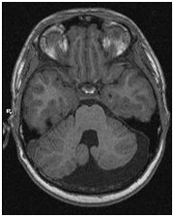

МРТ снимки мальформации Денди-Уокера